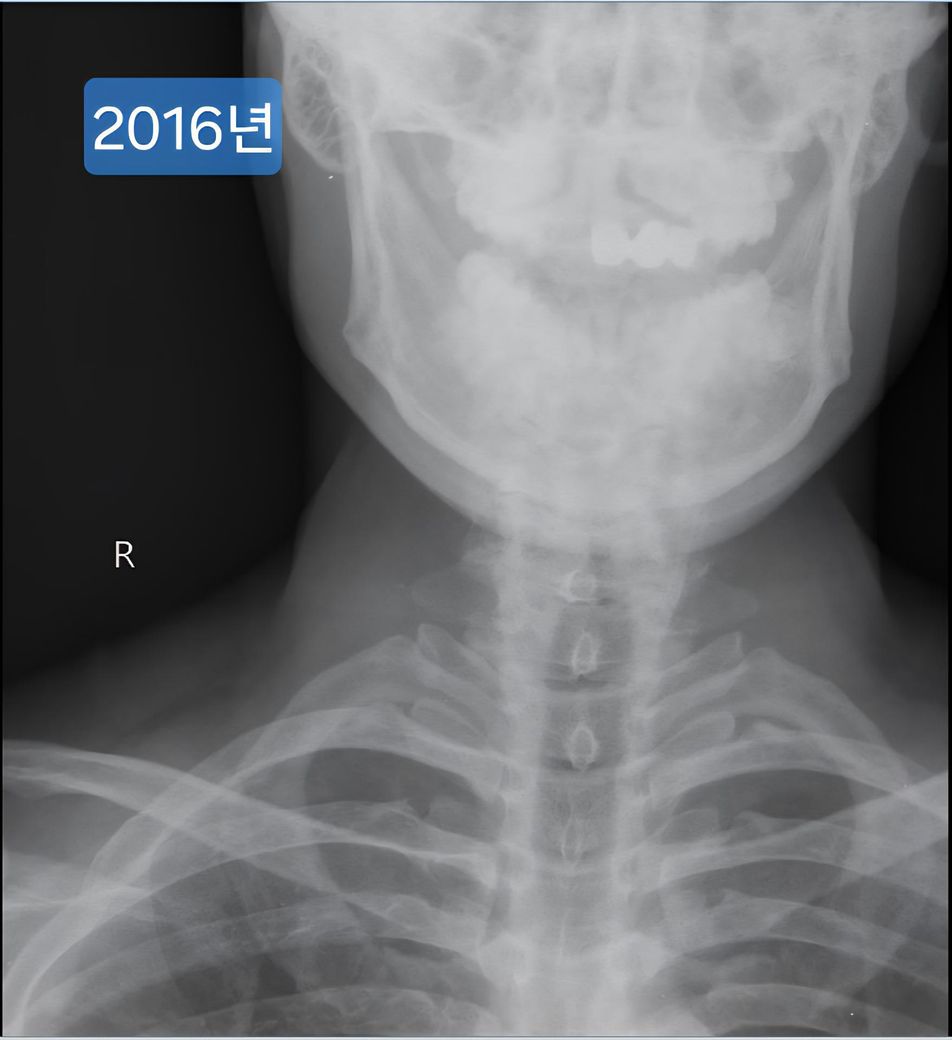

한 9년전에 이때도 운동하다가 어깨가 아파서 목과 어깨 엑스레이를 찍은 자료가 있더라구요.

며칠전 찍은 2025년도 엑스레이와 9년전 사진을 업로드 해 드리겠습니다.

(이미지에 좌측상단에 해당연도 표시했습니다.)

• 1번 째 사진